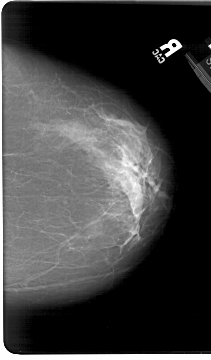

A_1386_1.RIGHT_MLO

RIGHT_MLO LINES 5746 PIXELS_PER_LINE 4156 BITS_PER_PIXEL 12 RESOLUTION 43.5 NON_OVERLAY